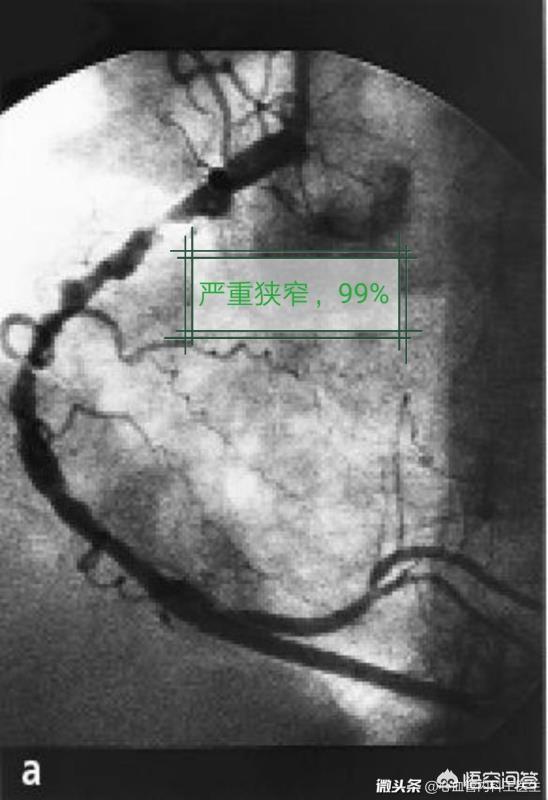

心臓ステントは冠動脈ステントとも呼ばれ、PTCA(経皮経管冠動脈形成術)手技で使用される器具である。心臓ステントは、体外では小さなメッシュ壁の金属チューブのように見え、ワイヤーとその前部のマイクロカプセルなどで構成されています。動脈ステントは動脈を支え、狭窄を解消し、スムーズな血流を確保する役割を継続的に果たすことができる。ステントは一般に急性心筋梗塞やその他の急性冠症候群の治療に用いられ、患者の生命を救ったり、生活の質を向上させたりする。

ステント内再狭窄はステントを留置した血管は、より長い期間(通常は数カ月から数年)をかけて、ゆっくりと再び閉塞していきます。このプロセスは非常にゆっくりなので、通常は心臓発作には至らず、最も一般的な症状は狭心症です。

現在のデータでは、ステント内再狭窄の5年発生率は全体で約10%である。

2、病変因子:血管のステント部位が分岐していたり、細かったり、非常に長かったり、曲がっていたりすると、再狭窄を起こしやすい。